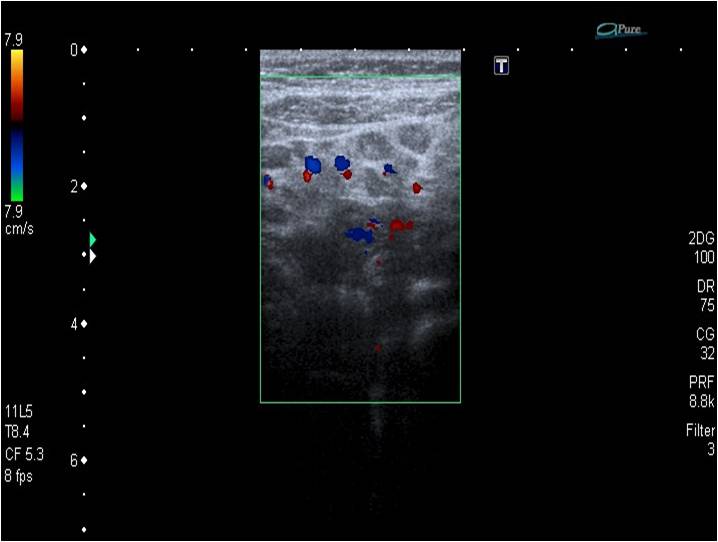

• Ecografía abdominal: hígado, vesícula y vías biliares, riñones, vía urinaria, vejiga, páncreas y bazo sin alteraciones. Las asas del intestino delgado y el colon muestran una pared de grosor normal y un discreto aumento de peristalsis. Llama la atención la hiperecogenicidad de grasa mesentérica, con múltiples y pequeñas adenopatías en su interior y un aumento de vascularización. Pequeña cantidad de líquido libre en fosa ilíaca derecha. Estos hallazgos sugieren, teniendo en cuenta información clínica, la posibilidad de enfermedad inflamatoria intestinal.